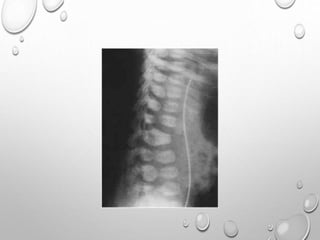

VERTEBRAE

LUMBOTHORACIC KYPHOSIS

LUMBER HYPER LORDOSIS

LENGTH GENERALLY NORMAL

PLATYSPONDYLY , DISC HEIGHT EQ TO VERTEBRAL BODY

POSTERIOR SCALLOPING

PEDICLES ARE SORT , THICK , INTERPEDICULAR DISTANCE DECREASED

ANGULAR KYPHOSIS AT THORACOLUMBER JUNCTION RESULTING FROM

ANTERIOR BEAKING OR BULLET NOSE VERTEBRAE

SPINAL CANAL STENOSIS ---- PATHOLOGIC HALLMARK